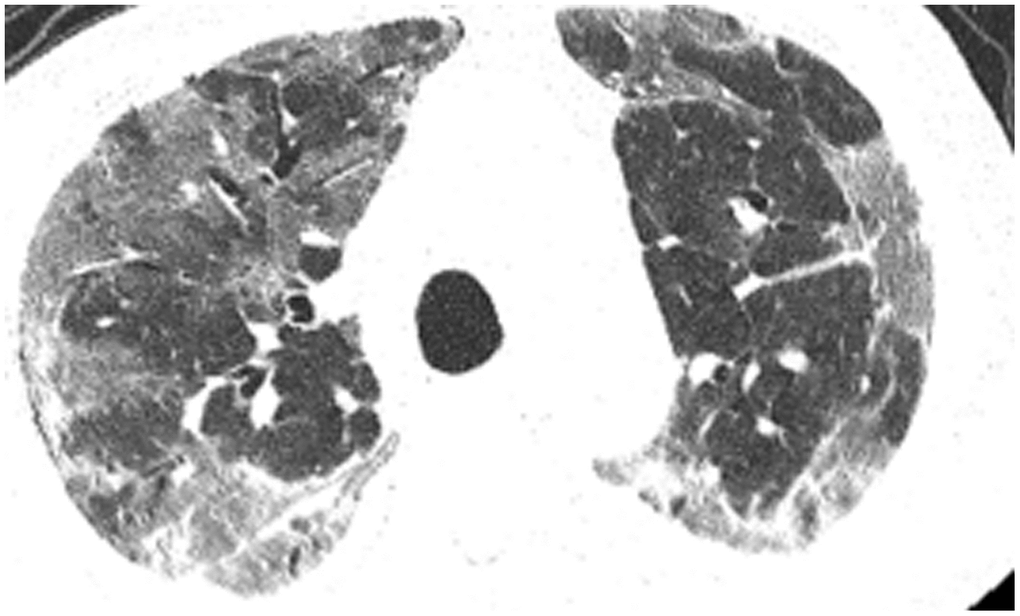

All patients were positive for the coronavirus nucleic acid test from pharyngeal swabs or blood. The blood lymphocyte counts and proportions of all patients were lower than normal (0.8×109/L) at the time of admission, and the white blood cell counts and proportions of six patients were higher than normal value (10×109/L). The blood D-dimer levels in all patients were higher than normal value (243 ng/mL) before neurological symptoms, and the C-reactive protein values in all patients were also higher than normal value (8000 μg/L). The chest CT of all patients showed flaky or frosted glass like- high-density shadow in lungs (Figures 1, 2), pleural effusion was seen in 2 cases (Figure 3), and no obvious abnormalities in 4 cases. The head CT imaging indicated that one patient had brainstem hemorrhage with ventricular cast and hydrocephalus (Figure 4), two patients had a large area of uniform low-density shadow on the frontotemporal lobe on the head CT (Figure 5), four patients had multiple flaky low-density shadow on the parietal lobe (Figure 6), one patient showed flaky low-density shadow in the pons (Figure 7), and three patients could see point-like low density shadow in basal ganglia (Figure 8).

Figure 1. Case 4, flaky or frosted glass like- high-density shadow in both lungs.

Figure 2. Case 5, focal high-density shadow in right lung.